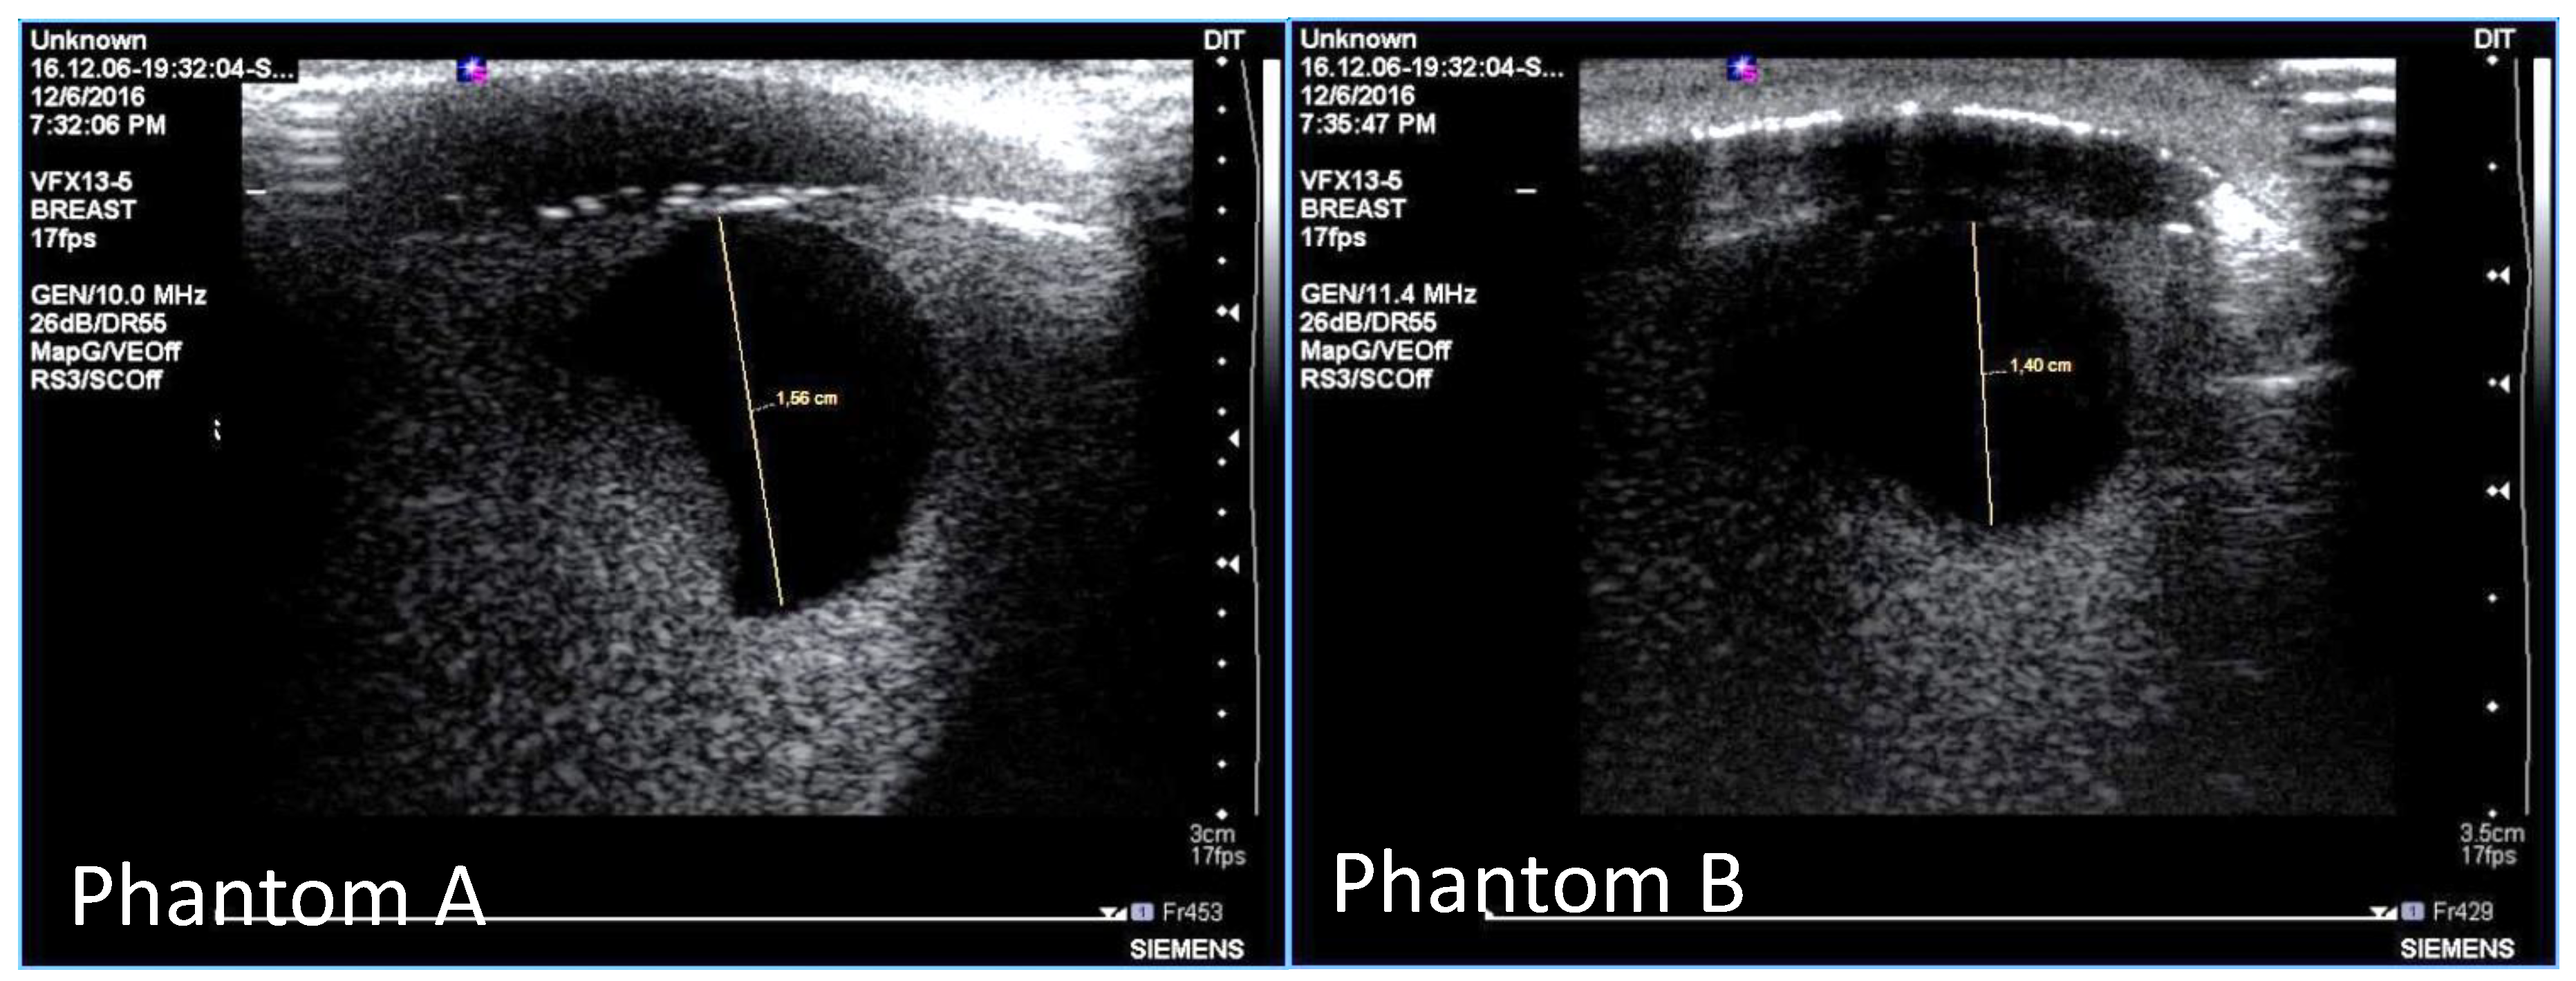

- B-mode ultrasound scanning was performed using an Antares scanner (Siemens, Germany) with a VFX13-5 linear array transducer at a nominal frequency of 10 MHz. The output power was set to maximum and three focal zones were positioned at 10, 15 and 20 mm, which represented the entire length of the lesion. The maximum depth and FOV was set to 35 mm, which is representative of clinically relevant depth for breast ultrasound imaging. Representative ultrasound images of Phantom A and B are presented in Figure 6. All the layers can be distinguished, except for the pectoral muscle layer, which does not intersect with the scanning plane as this was beyond the typical clinically relevant field of view. Moreover, the indents in the tumor shape in Phantom A were accurately depicted in the ultrasound image. A mismatch in terms of speed of sound between the reference value (1479 ± 32 m/s) and the achieved one (1710 ± 17 m/s) for the breast fat, resulted in an underestimation of the thickness of the fat layer in the ultrasound image. This feature also occurs in clinical imaging where Coopers ligaments are present at the interface between fat and fibroglandular tissue; more importantly an accurate clinical contrast was achieved between the fibroglandular tissue and the tumor, with the tumor mimic being presented as a hypoechoic region within the image [45].